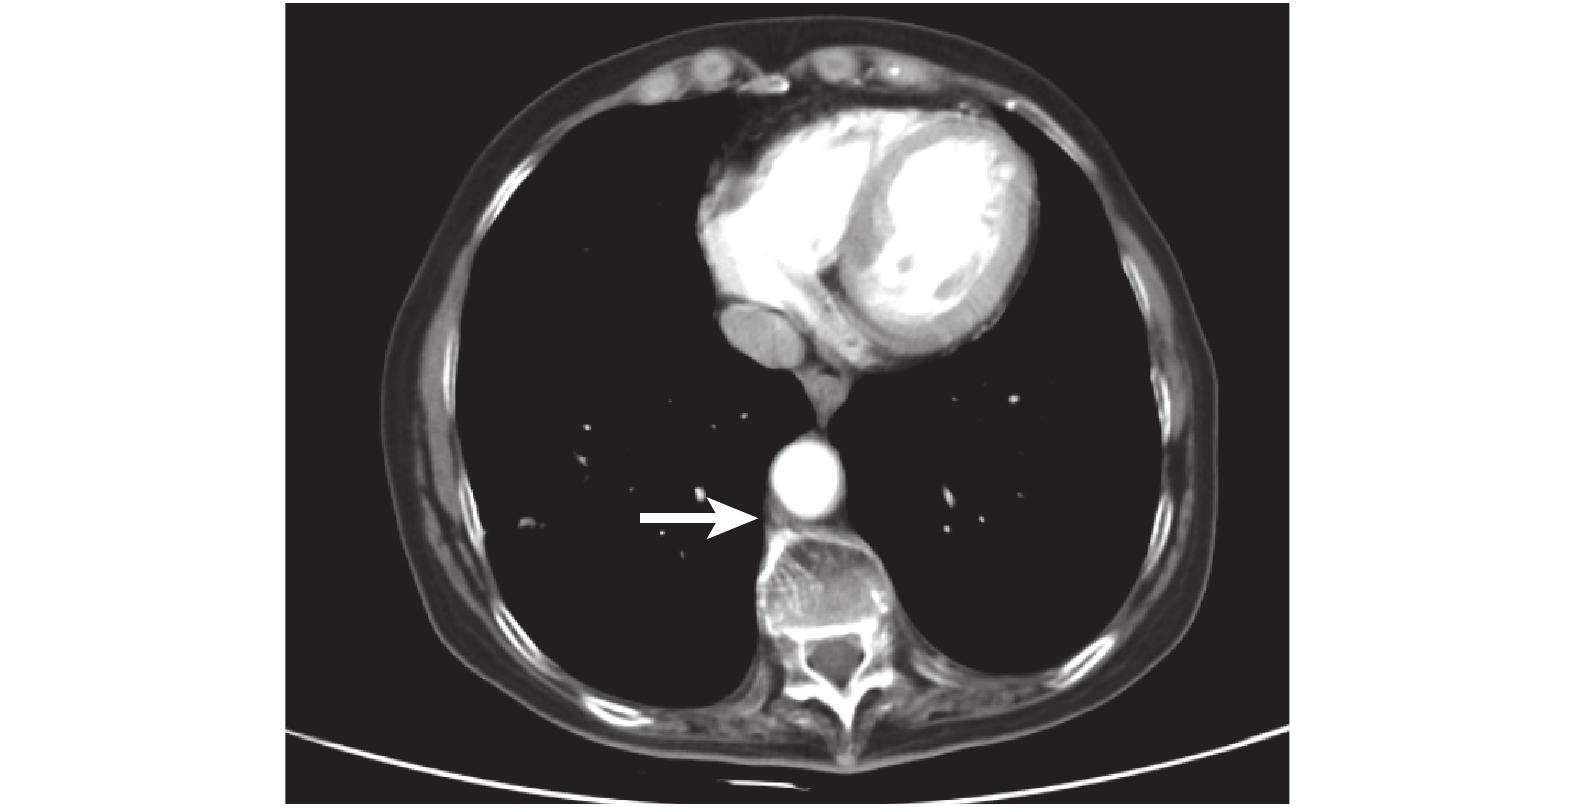

病例 3:患者,女,72 歲,患者進食梗阻感 1 個月為主訴入院治療,外院胃鏡示:距門齒 20 cm,占位 5 mm×4 mm,PET-CT:食管腔內占位,CT 顯示食管上中段局部管壁不規則增厚,最大層面 2.3 mm×2.0 mm,侵及長度為 4.5 cm,局部管腔狹窄,狹窄以上食管輕度擴張,CT 值為 29~47 Hu,結論為食管上中段癌可能(圖 3)。食管鏡顯示:距門齒 20~23 cm,見左壁占位性病變,傘形,窄蒂,診斷為食管占位性病變(圖 4)。吞鋇餐見食管胸中段長約 1~2 個椎體充盈缺損,診斷為食管胸中段癌。患者于全身麻醉下行食管腫瘤套切術,術后 3 個月隨訪,生活質量良好,術后 2 年隨訪患者腫瘤復發死亡。